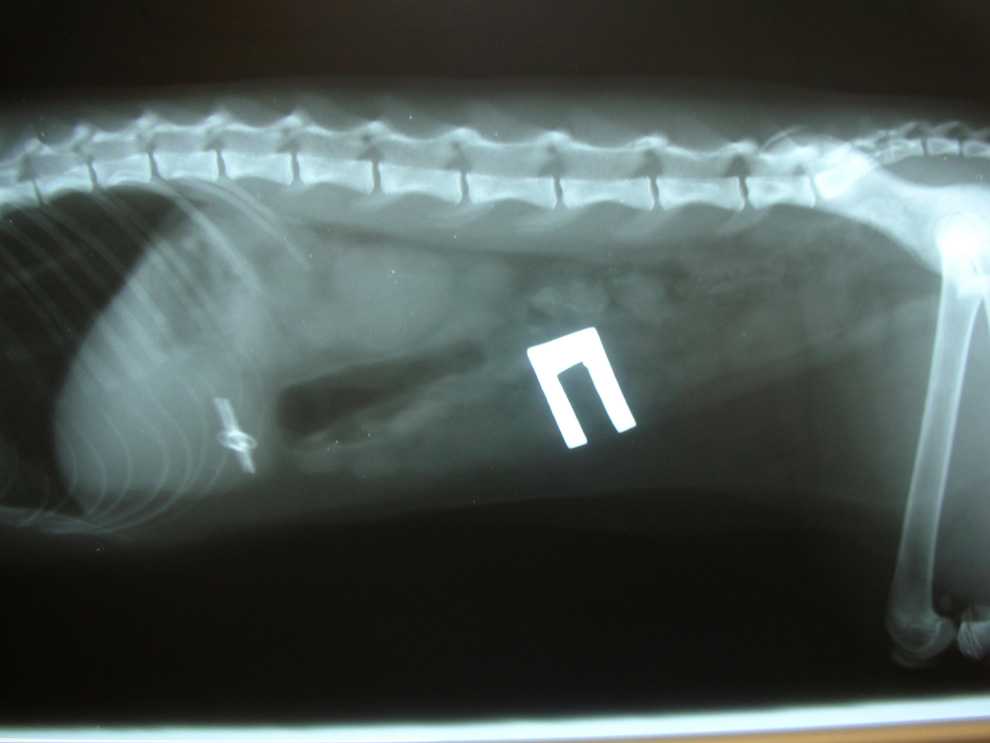

Свободное движение инородного тела в кишечнике не вызывает у собаки каких-то отклонений в ее состоянии, животное чувствует себя нормально. Но стоит только инородному телу застрять в просветах кишечной трубки, то у собаки сразу начинает развиваться кишечная непроходимость. У нее появляется рвота, она отказывается от корма, состояние животного угнетенное, кишечник вздут, при проведении пальпации живота собака чувствует боль. Анамнез, клиническая картина, паранефральная блокада и рентгенография помогают установить точный диагноз. Часто инородное тело можно прощупать даже через брюшную стенку.

Собаке, проглотившей инородный предмет, в клиники сделают эпиплеваральную или паранефральную блокаду. Если это не приведет к положительным сдвигам, то животному вскрывают брюшную полость. Застрявший предмет удаляют через рассечение или разрез кишки. Рана брюшной стенки зашивается обычным порядком, как и при любой операции. После этого собаке назначаются антибиотики и диета из продуктов, которые собака сможет легко переваривать: бульоны, молоко, слизистые отвары из геркулеса и риса. Маленькие острые предметы мигрирующие по кишечнику животного удаляются только после того как с помощью рентгенографии будет установлена их локализация.

При посещении клиники ветеринар сначала осматривает собаку. Сразу обнаружить инородное тело можно, если оно застряло в глотке. Если проглочен крупный и твердый предмет, его можно нащупать при пальпации брюшной полости. В остальных случаях применяется инструментальная диагностика.

- Рентгенография поможет выявить наличие металлических, резиновых предметов, камней. На рентгене также видна деформация и другие изменения в органах пищеварительного тракта, характерные для присутствия инородного тела.

- Рентген. Во время исследования бывают хорошо видны камни, металлические и резиновые предметы. Или же, если инородное тело не определяется, врач может заметить изменения внутренних органов, характерные для наличия инородного тела.